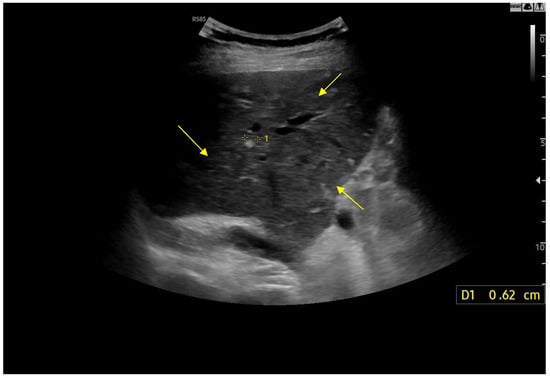

Figure 5.

Linear Probe (9 MHz) with trapezoidal scan. Diffusely dense and heterogeneous echostructure due to the presence of multiple and diffuse hyperechoic areas, suggestive of peri-portal fibrosis.

Doppler patterns in Fontan patients resemble those observed in chronic liver disease, including reduced portal flow velocity (mean flow velocity < 14 cm/s) [56]. The Fontan procedure inevitably alters hepatic venous waveforms on Doppler US (Figure 10, Figure 11, Figure 12 and Figure 13). Inverted portal flow has a specificity of 100% for diagnosing PHTN [57] (Figure 12). The hepatopetal phase pattern in the hepatic vein differs between patients with total cavo-pulmonary anastomosis (including both lateral tunnels and extracardiac conduits) and those with atrio–pulmonary connection [58,59,60]. In atrio–pulmonary connection, hepatopetal flow is preserved (Figure 10), reflecting the exclusion of atrial contribution to venous circulation, whereas in total cavo-pulmonary anastomosis, flow reversal (Figure 11) occurs only during early expiration. Similarly to congestive heart failure, hepatic veins and the IVC are dilated, with abnormally increased hepatic vein pulsatility, regardless of the anastomosis technique [54,61,62]. The loss of the normal three-phase Doppler pattern in hepatic veins is universal following bi-cavo-pulmonary surgery due to the absence of atrial contraction. The presence of a monophasic pattern indicates advanced liver injury [63].